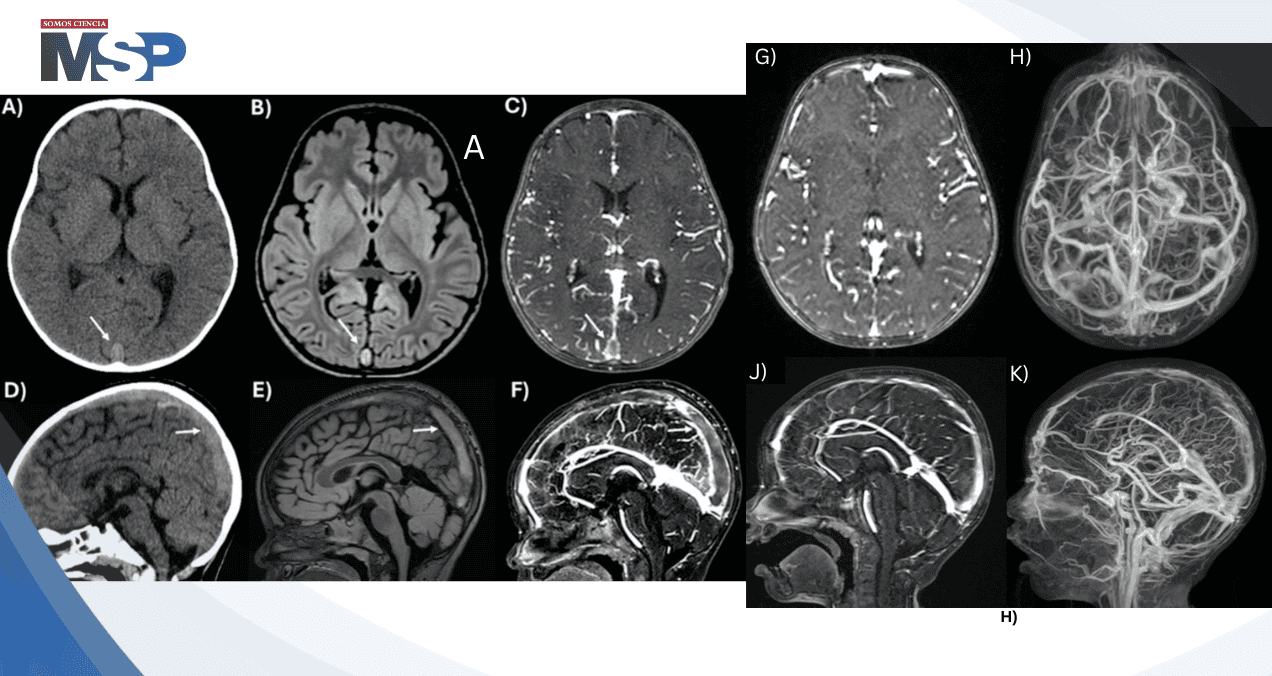

La tomografía computarizada craneal sin contraste mostró un seno sagital superior heterogéneo, hallazgo que fue confirmado mediante resonancia magnética cerebral y venografía por resonancia magnética, las cuales demostraron trombosis del seno transverso derecho, seno sagital superior y venas corticales adyacentes.

El seguimiento a los tres meses demostró resolución casi completa de las trombosis venosas en estudios de neuroimagen. La anticoagulación con heparina de bajo peso molecular se mantuvo durante cinco meses desde la presentación inicial.